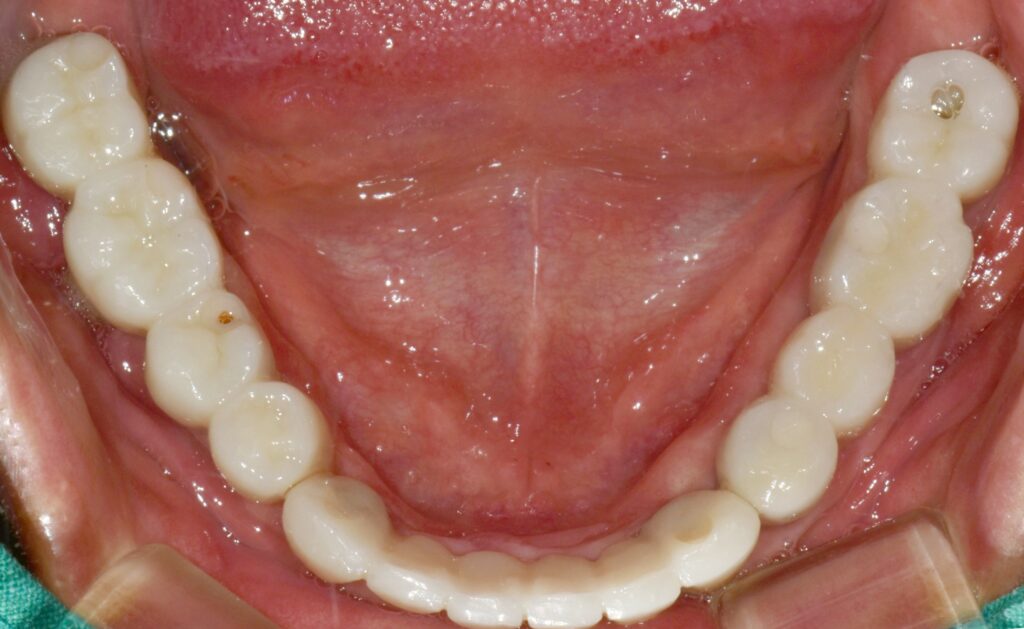

최종 보철물로 이행

임시 치아 기간을 대략 한 달에서 두 달 정도 갖고 모든 것이 다 좋다고 판단될 때 인상채득을 해서(본을 떠서) 최종 보철물로 이행을 해줍니다.

조화롭게 치료가 잘 된 모습입니다. 당연히 식사도 편하게 잘하시고 그 덕분에 생활에 활력이 넘치고 일이 잘 풀린다고 하셨습니다.